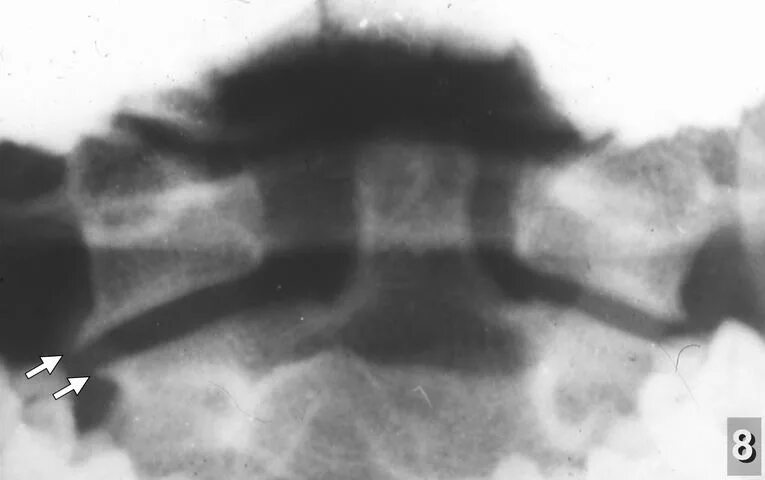

Подвывих по ковачу